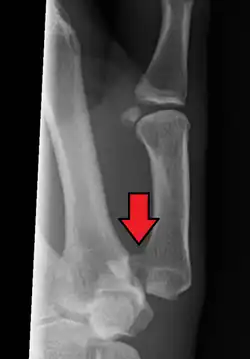

Bennett's fracture

The Bennett fracture is an oblique intraarticular metacarpal fracture dislocation, caused by an axial force directed against the partially flexed metacarpal. This type of compression along the metacarpal bone is often sustained when a person punches a hard object, such as the skull or tibia of an opponent, or a wall. It can also occur as a result of a fall onto the thumb. This is a common injury sustained from bike falls, as the thumb is generally extended while around the handle bars. It is also a common injury in car crashes, especially into fixed objects, from the driver holding the steering wheel during impact. The hand moves forward, while the steering wheel rim hyperextends the thumb. Some authors have recently made an assertion against popular belief that the APL tendon is not a deforming force on the Bennett fracture.[3]